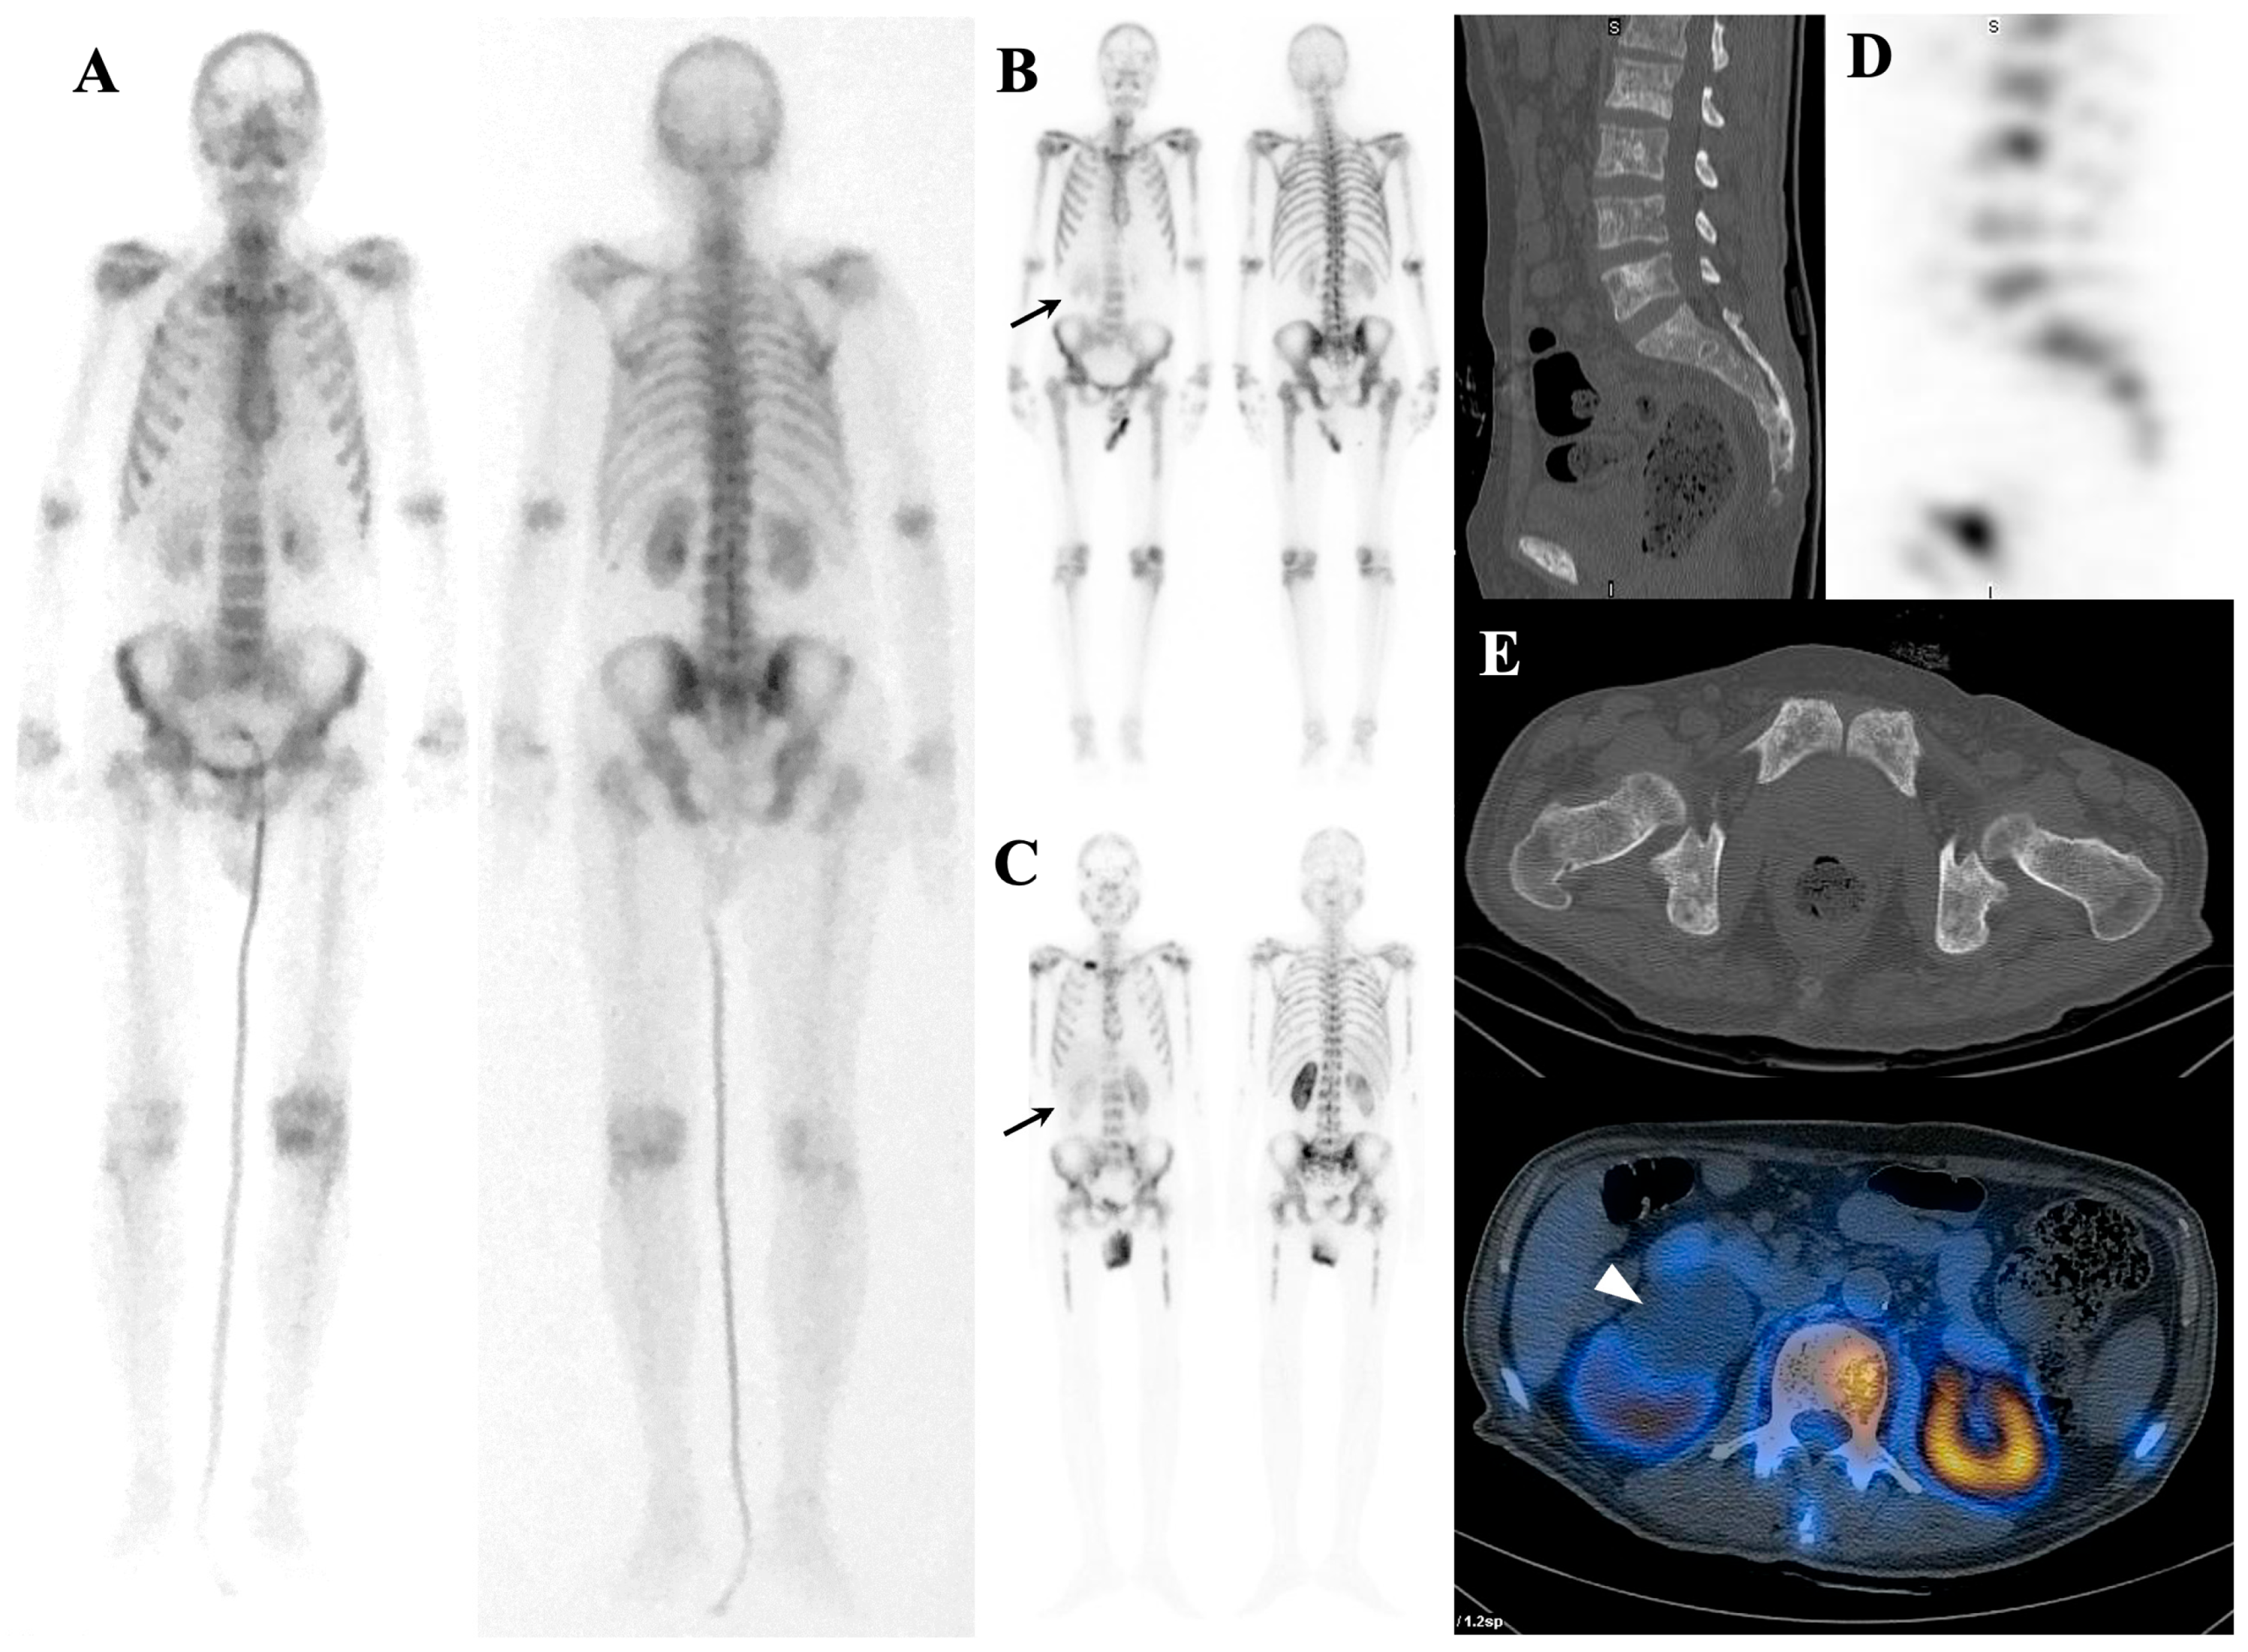

7.1.2. Dynamic Changes in Prostate Cancer Patients with Superscan